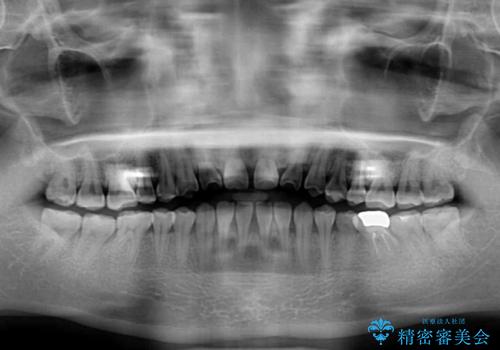

- 上下の前歯の隙間を気にして来院された患者様です。

インビザラインを用い、上下歯列のスペースを閉じていくこととしました。

治療期間中は奥歯がほとんど咬めない状態が続き、食事に大変苦労されました。

最終的には隙間もしっかりと閉じ、奥歯も咬みやすい状態でしあげることができました。